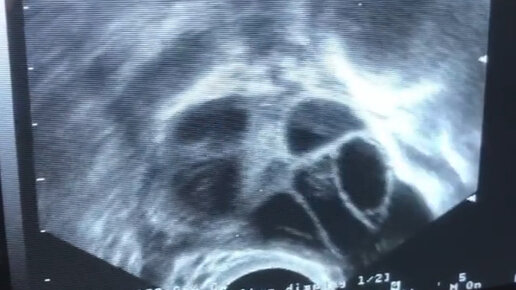

Пункция фолликулов

Центр ЭКО Меркурий